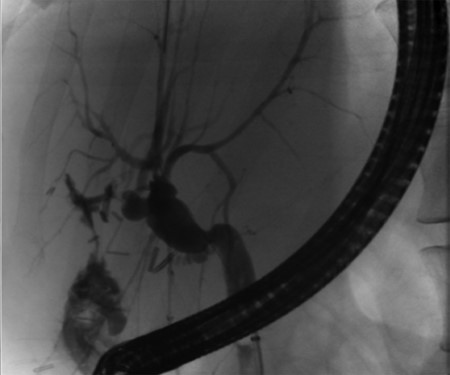

Independent biliary duct (blue arrow) draining to the cyst and not to the liver parenchyma.

A 35-year-old female with a medical history significant for acute biliary pancreatitis status post laparoscopic cholecystectomy, presented to the surgery clinic as a new consult for a large cystic liver mass with increasing abdominal pain for 2 weeks. Patient reported suffering from severe pain in right chest, shoulder and diffuse abdominally that worsened with standing. Patient complained of inability to inspire due to pain and a 10-pound weight gain over 2 months. She confirmed decreased appetite especially with solids, nausea and emesis, alternating constipation and diarrhea, bruising, and pruritus at night. Computed tomography (CT) scan demonstrated a peripherally septated 10 x 7 cm cystic mass in the liver with intrahepatic biliary dilation (Fig. 1). The patient was referred for endoscopic retrograde cholangiopancreatography (ERCP) to establish preoperative biliary anatomy and was found to have moderate compression of the common hepatic duct managed with a right hepatic biliary endoprosthesis (Fig. 2); no obvious communication of the biliary tree with the cystic lesion was seen. Patient symptoms persisted despite optimizing with a protein-rich liquid diet; thus, the decision was made to proceed with the surgical plan for an open partial central hepatectomy. The patient was taken to the operative theater. After induction of general anesthetic, an upper midline incision was made. Inspection of the abdomen and liver showed no metastatic lesions grossly or with ultrasonographic imaging. The cyst was visible upon entry into the abdomen with no solid component to the mass in proximity to the cystic neoplasm. The second portion of the duodenum was adherent to the cyst with inflammatory adhesions and was quite boggy. A partial central hepatectomy was performed; a 3 mm biliary duct was found communicating to the cyst only with no drainage to the minimal liver parenchyma that was removed (Fig. 3). The cyst was resected en-bloc and was sent for permanent section (Fig. 4), which diagnosed the tumor as a low-grade mucinous cystic neoplasm measuring 8.5 × 7.2 × 6.4 cm. Microscopy revealed a smooth-walled, multiloculated cyst filled with a yellow-golden, semi-transparent and mucinous fluid (Fig. 5a–c). The cyst was lined by a mucinous epithelium with ovarian-type stroma. No high-grade dysplasia or malignancy was identified. The postoperative course was uneventful, and the patient was discharged on postoperative day 6. At the 4-week postoperative visit, the patient was healing well with some incisional soreness; patient was seen for removal of her biliary endoprosthesis, and ERCP found left sided intrahepatic duct biliary dilatation including a small biliary fistula from the left system (Fig. 6) with the appearance of torque on the extrahepatic biliary tree. A biliary endoprosthesis was left in place, and the patient returned for repeat ERCP 4 weeks later with resolution of all findings (Fig. 7). At present, patient remains alive with no signs of recurrence.